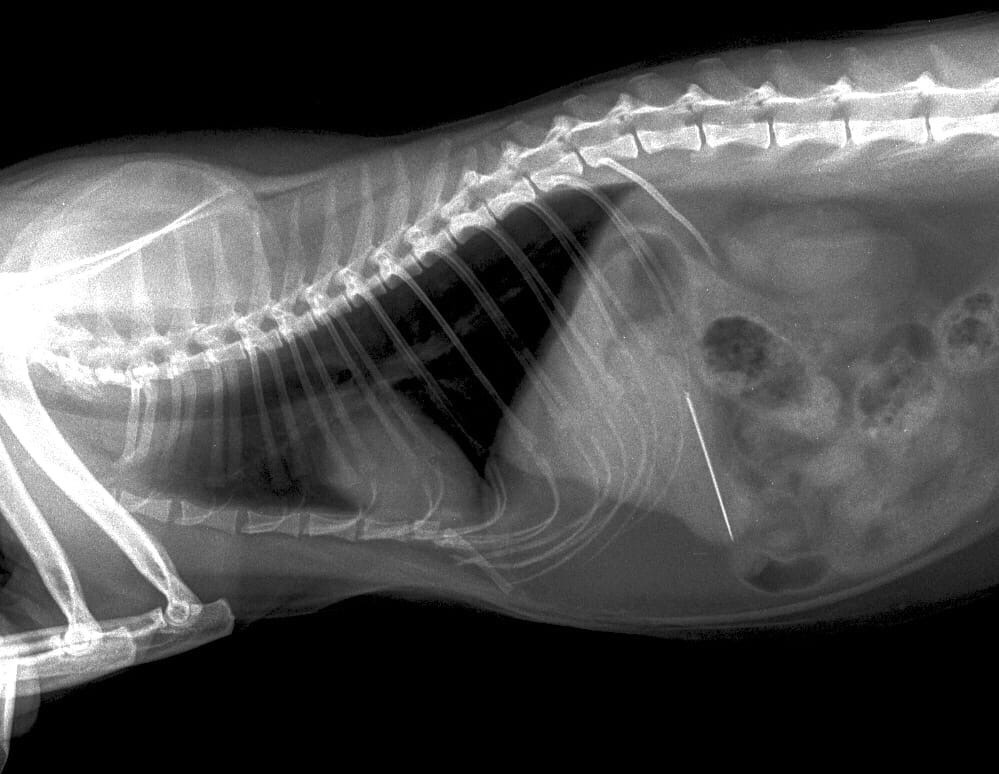

Со сложным и вместе с тем интересным клиническим случаем столкнулись недавно врачи ветеринарной клиники «Биосфера». Любимец хозяев играл и вытащил из коробки со швейными принадлежностями нитки. Кошки — большие любители игр с пакетиками, веревочками, нитками и прочими опасными штуками. «Охота» кота обернулась неудачей. Он проглотил с ниткой иголку и был оперативно доставлен хозяевами в ветклинику. Дать четкий ответ могло лишь эндоскопическое исследование. Погрузив животное в наркоз, провели экстренную гастроскопию (исследование пищевода и желудка).

Исследование показало, что иголка встала горизонтально в желудке. Благодаря мастерству эндоскописта инородное тело было извлечено. В наркозе животное провело недолго и избежало самого опасного и тяжелого – длительной, изнуряющей операции.